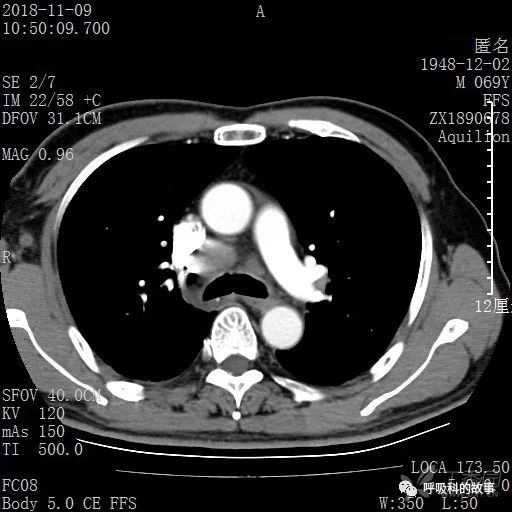

胸部增强CT示右肺门占位伴远端阻塞性肺炎,纵膈、右肺门、右侧颈根部、右侧腋下及肝门部肿大淋巴结。两侧胸腔少量积液。

纵隔窗的增强CT

肺窗CT